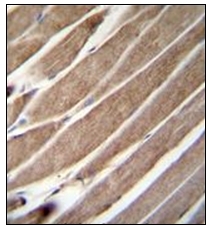

Supportive validation

- Submitted by

- OriGene (provider)

- Main image

- Experimental details

- Formalin Fixed, Paraffin Embedded Human skeletal muscle stained with ATG4D Antibody (N-term) ??followed by peroxidase conjugation to the secondary antibody and DAB staining.

- Validation comment

- IHC